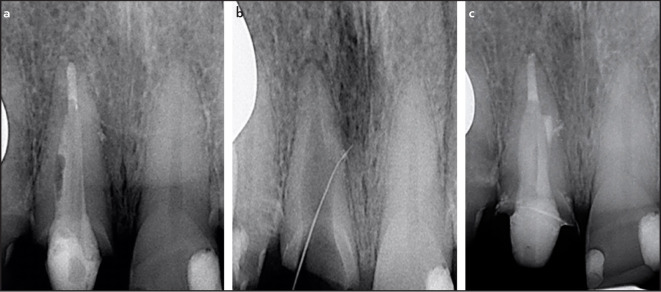

This is a series of 7 cases in which the operator penetrated lateral canals with instruments. Two teeth presented with irreversible pulpitis, 4 with necrotic pulps, and 1 with previous treatment. Except for the teeth with pulpitis, all the others were associated with apical periodontitis. The main root canal was always relatively straight, with the lateral canals at the middle third of the root. Suggestive images of lateral canal presence were seen on periapical radiographs in five cases. The clinician introduced intentionally small hand instruments in the lateral canal in 5 cases, while the penetration was fortuitous in the others. The lateral canals were obturated in all cases. Follow-up examination was possible in five cases, all of them showed evidence of successful clinical and radiographic outcomes. Introducing files into lateral canals may permit some preparation and penetration of irrigant solution, favoring disinfection and, consequently, enhancing the treatment outcome. (EEJ-2023-05-063).

Abstract Image